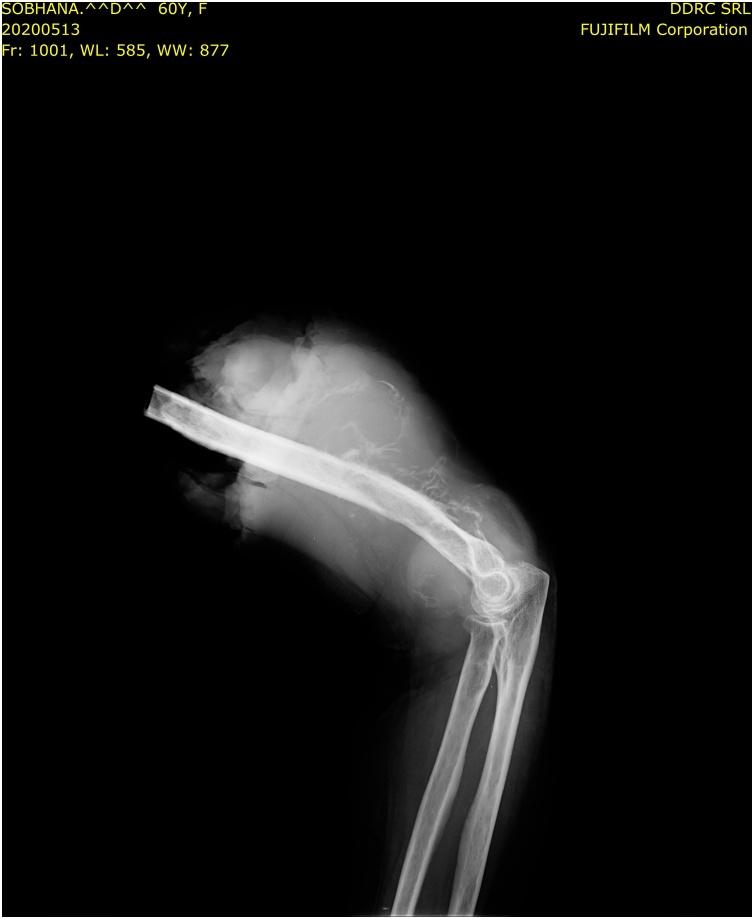

A 48 year old female presented initially with a localised swelling of 2 cms diameter in the front of the left elbow in 2007, which was excised. It recurred repeatedly and was excised. In the earlier presentations, the swellings were firm, mobile and not fixed to bone. In the last stage alone, bone fixity was identified. All the fourteen surgeries were performed by the primary author from 2007 to 2020, as the patient was particular. THE MAIN CLINICAL DIAGNOSES: had been neurofibroma and fibrosarcoma. There was no evidence of distant metastasis all these years. She did not respond to radiation or chemotherapy. Initially it was single, but later multiple. She had no clinical features of Neurofibromatosis 1 (NF1) or any family history. As the history progressed, the swellings became muscle deep and later encircled the radial nerve. The radial nerve was salvaged on three occasions. On the last three occasions, the tumour had to be shaved off from the humerus. The final amputation specimen showed a single tumour infiltrating the humerus and x-ray revealed bone destruction and tumour calcification. Final diagnosis was aided by immunohistochemistry (IHC) and cytogenetic study (FISH).

一名48岁女性于2007年首次就诊,左肘前部出现一个直径2厘米的局限性肿块,该肿块被切除。它反复复发并被切除。在早期表现中,肿块质地坚硬、可活动,未与骨骼固定。仅在最后阶段才发现与骨骼固定。从2007年到2020年,所有14次手术均由第一作者进行,因为患者比较挑剔。主要临床诊断曾为神经纤维瘤和纤维肉瘤。这些年来均无远处转移的证据。她对放疗或化疗均无反应。最初是单发,但后来变为多发。她没有神经纤维瘤病1型(NF1)的临床特征或任何家族史。随着病程进展,肿块深入肌肉,后来环绕桡神经。桡神经曾三次得以保留。在最后三次手术中,不得不从肱骨上刮除肿瘤。最终截肢标本显示单个肿瘤侵犯肱骨,X线显示骨质破坏和肿瘤钙化。免疫组织化学(IHC)和细胞遗传学研究(FISH)辅助做出了最终诊断。